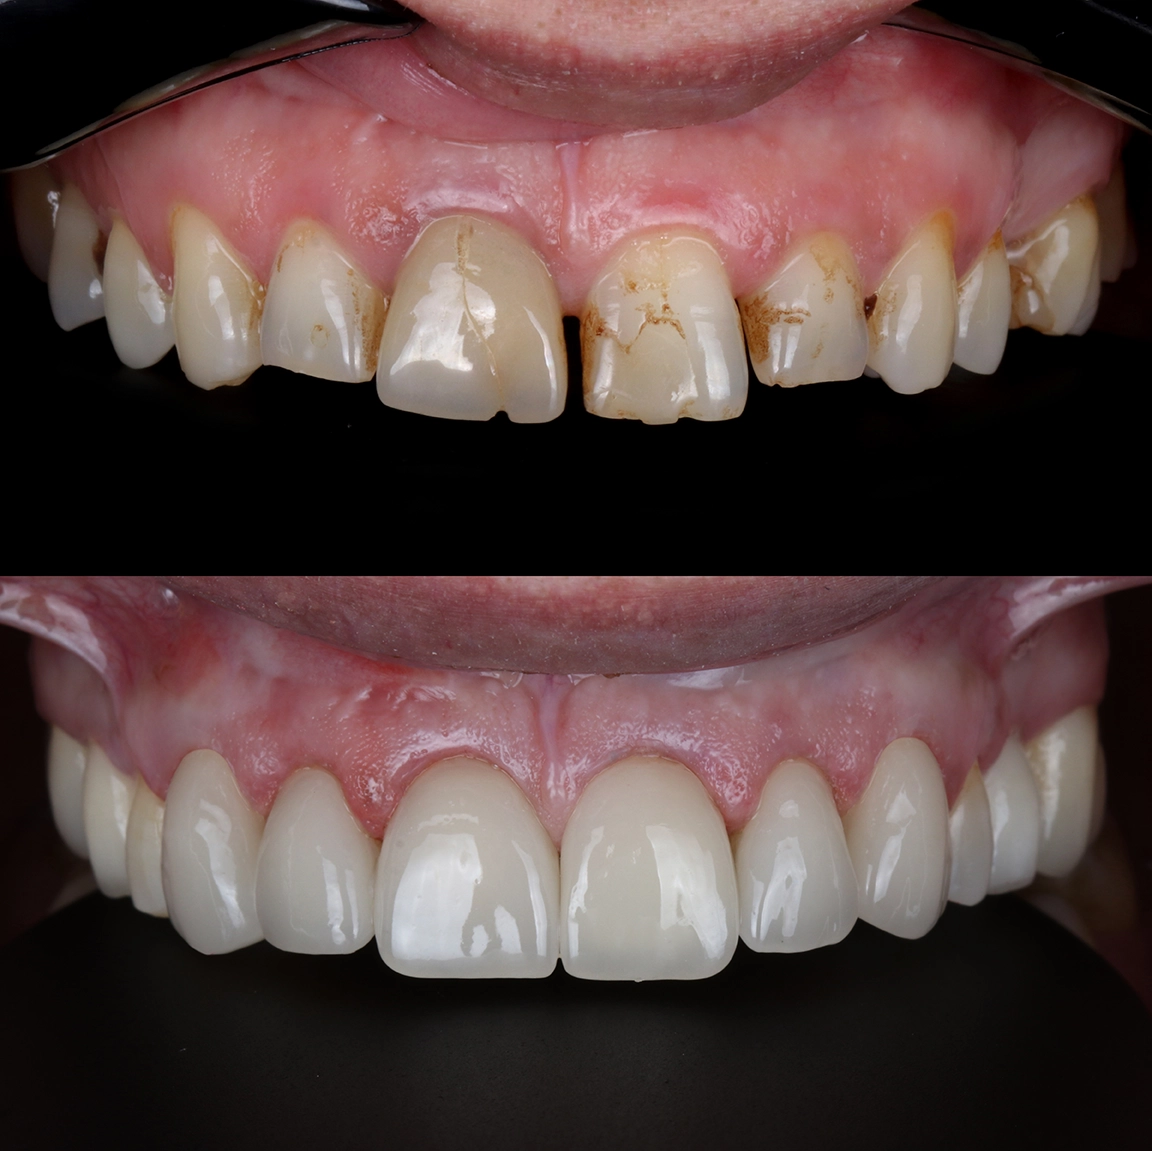

Risultati